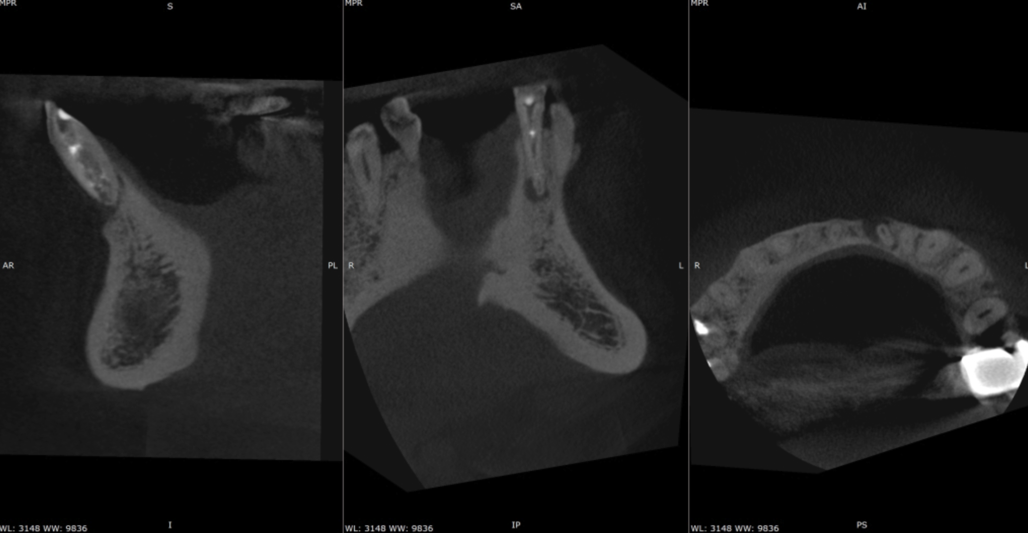

Key findings from CBCT Consultant radiologist’s report by JM Radiology:

- LL1 is mesially rotated

- There is a large, irregularly shaped root canal with fragments of dressing within it.

- It is unclear whether this canal has been partially shaped or if there is a degree of resorption resulting in its widened appearance, if this is resorption the entire length of the root canal is affected.

- There is mild apical resorption of the LL1 resulting in two apical exit points.

- There is a well-defined area of apical radiolucency measuring approximately 5mm (w) x 3mm (d) x 9mm (h).

- There is dehiscence of the labial cortex overlying the root of the LL1 (BIG LESION!)

CBCT assessment confirmed the tooth was restorable however, the patient was consented for the possibility of root-end surgery (RES) should the case fail to heal adequately following an orthograde approach. The treatment was completed over 2 visits and involved an inter-visit dressing with calcium hydroxide which saw full resolution of the buccal sinus tract after a 3-week period. Preparation was carried out using Dentsply’s Wave one gold rotary files up to size medium. It was then obturated with Totalfill BC sealer Hiflow and conform fit GP cones that were customised using a gp cutter to ensure a nice apical fit in view of the apical resorption.